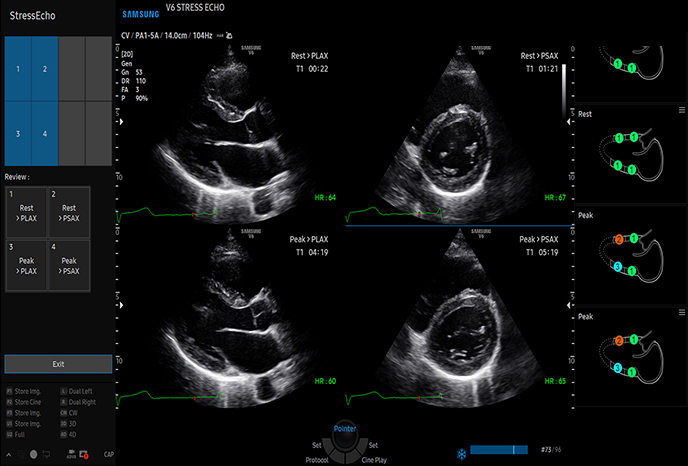

하이앤드 초음파 장비를

활용한 정밀 심장 검사

심장 질환 진단에서 가장 중요한 것은 ‘심장의 상태를 얼마나 정확하게 볼 수 있느냐’입니다. 저희 센터는 대학병원급 하이앤드 초음파 장비를 도입하여, 실시간 3D 렌더링으로 정밀 진단이 가능하며, 심장의 구조·혈류·기능을 실시간 고해상도로 관찰합니다.

미세한 판막 움직임, 혈류 속도 변화, 심방·심실 크기와 수축력까지 정밀하게 분석할 수 있어, 심장질환의 조기 발견과 치료 계획 수립에 큰 차이를 만듭니다.